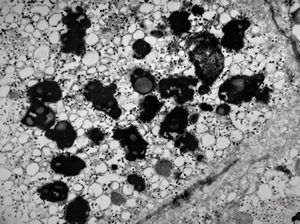

M,2y. | dense mitochondrial inclusions - clinically susp. Zellweger syndrome